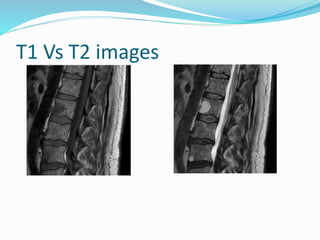

 T1 weighted image

 Longitudinal relaxation time

 Short TR and short TE

 return of protons back to equilibrium after application

and removal of the RF pulse

 Good anatomic detail- sharp / well defined

 Fat- bright ; Fluid – dark

 Contrast Enhanced MRI are T1 weighted

 T2 weighted image

 Transverse relaxation time

 Long TR and long TE

 Associated loss of coherence or phase b/w individual

protons immediately after application of RF pulse

 Evaluation of pathological process/ sensitively detect

edema

 Fat – bright ( fatty tissue/ bone marrow)

 Fluid – brighter ( CSF/ fluid)

T1 Vs T2 images